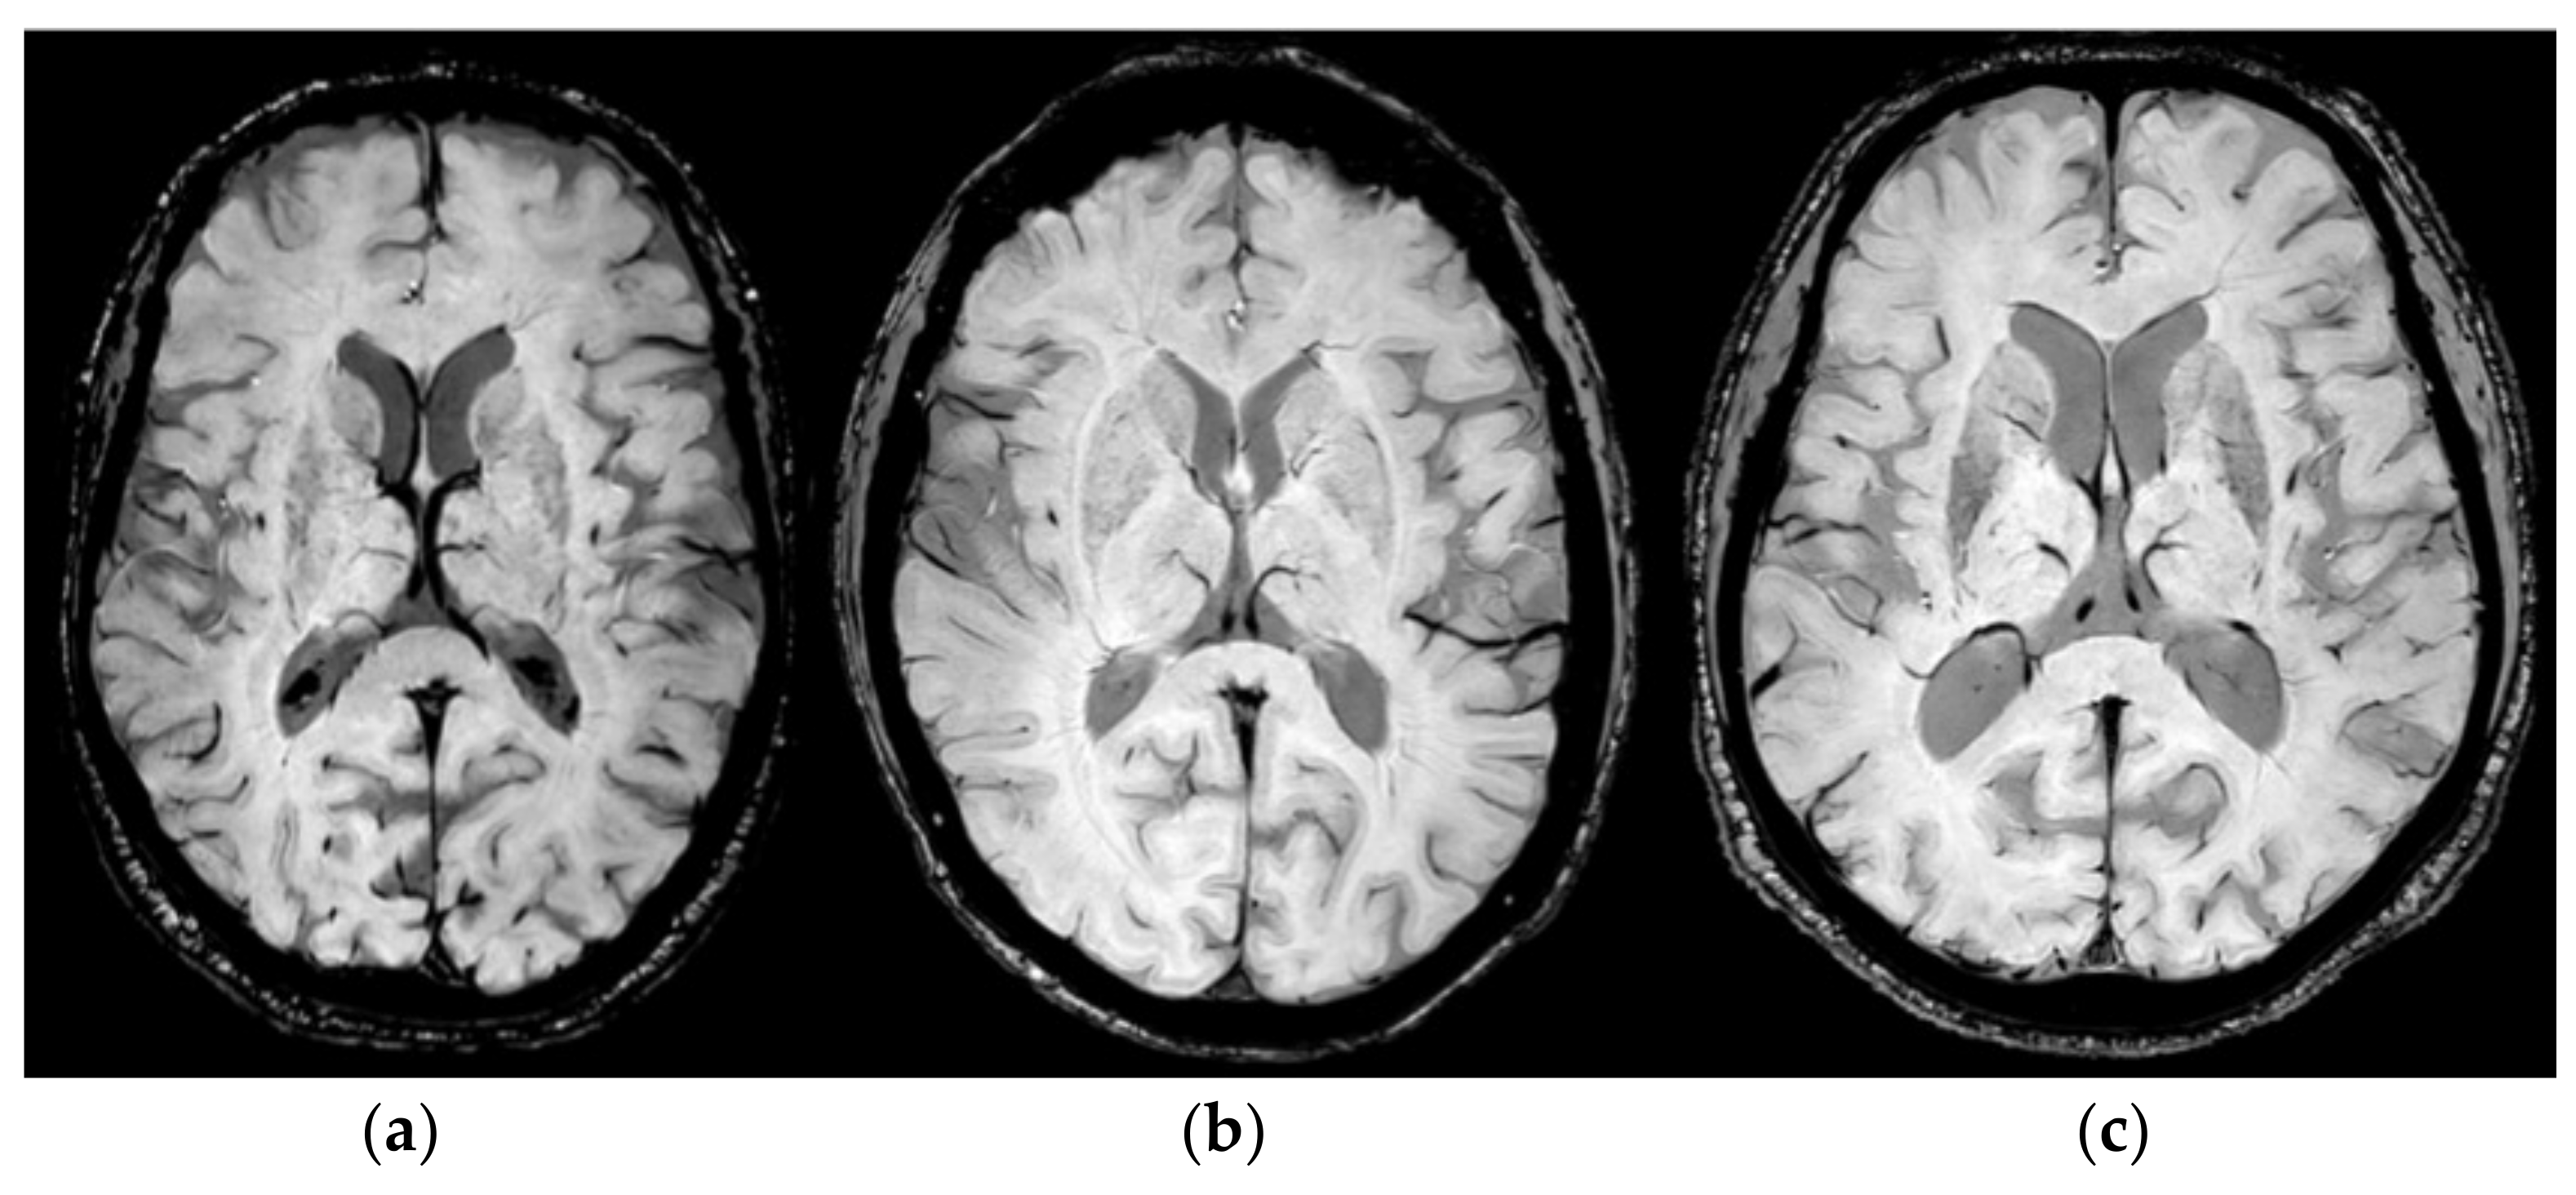

In Figure 4, examples of the detected STV variants from three different patients and those obtained by using SWI sequences are reported. In Figure 4a, it is possible to observe the Type 1A variant in which the STV drains into the anterior portion of the ICV; in Figure 4b, the Type 1 B variant, in which the STV drains into the posterior portion of the ICV, is depicted; and in Figure 4c, the variant Type 3 A is shown, in which drainage occurs in the medial atrial vein.

Figure 4.

Example of STV variants obtained by using SWI MR sequences for three different patients enrolled in this study. (a) Related to Type 1 A variant; in (b), Type 1 B variant is shown; and, in (c), Type 3 A variant is depicted.